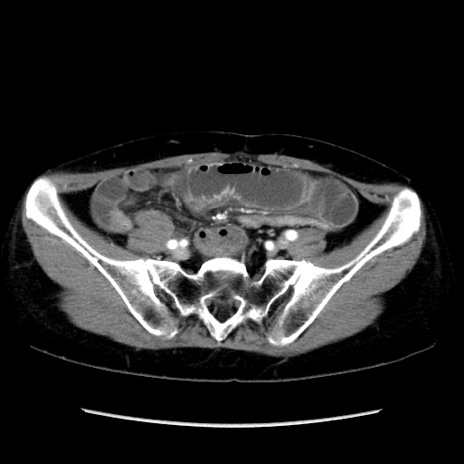

症例32(横断像)

【症例】40歳代 女性

【主訴】上腹部痛、嘔気・嘔吐

【現病歴】約9時間前頃から急に上腹部痛、嘔気、嘔吐が出現。改善しないため救急要請。

【既往歴】子宮頚癌(広汎子宮全摘術、放射線療法)、腸閉塞

【身体所見】腹部:平坦、軟、腸雑音亢進、上腹部を中心に腹部全体に圧痛あり。

【データ】WBC 8400、CRP 0.03